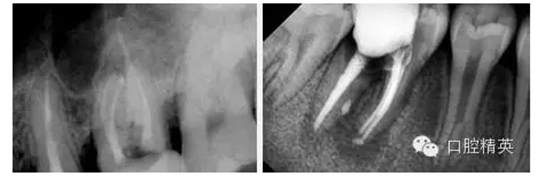

熟悉根管解剖結(jié)構(gòu)是根管治療的先決條件,通常中切牙到第二前磨牙根管尋找容易。上頜第一磨牙最新的根管解剖研究認(rèn)為其近頰根扁而彎常有兩個(gè)根管和管間交通支存在,近頰第二根管(MB2)根管口隱蔽,根管細(xì)彎,臨床治療率低,難度大是上頜磨牙治療失敗的主要原因。臨床上應(yīng)該加以高度重視。

新的研究上認(rèn)為上頜第一、二磨牙近頰根管變異大,近頰可以有1-3個(gè)根尖孔,近頰根主根管(MB1)位于根尖頂者近一半,MB2位于根尖頂者上頜第一磨牙約為7%,上頜第二磨牙約為26%,各型根尖孔多位于根尖遠(yuǎn)中或舌側(cè)。MB2根尖孔到解剖根尖約1.5-2.5mm第一磨牙平均2.03mm,第二磨牙平均1.82mm,MB2在工作實(shí)踐中在確定根管工作長度時(shí)不能常規(guī)的以距根尖孔0.5-1.0mm作為測量標(biāo)準(zhǔn)。

多數(shù)MB1、MB2的根尖1/3彎向遠(yuǎn)中,MB2在近根管口1-3mm處明顯彎向近中,,根管中段較直,研究顯示MB2在離體上頜第一磨牙的出現(xiàn)率近90%,臨床上通過將上頜第一、二磨牙開髓口改良為斜四邊形及去除髓腔近中壁牙本質(zhì)懸突可提高M(jìn)B2的出現(xiàn)率。

下頜第一磨牙近中根95%為雙根管,遠(yuǎn)中根46%為雙根管,所以常有3-4個(gè)根管。頰舌各一,其管間牙本質(zhì)在根部冠1/3較薄向根端逐漸增厚。下頜第二磨牙近中根49%為雙根管,遠(yuǎn)中根多為單根管,下頜第二磨牙C型根管系統(tǒng)發(fā)生率很高,為15.8%~45.5%,由于根管形態(tài)復(fù)雜,及較高的副根管,交通支根尖三角等根管變異的發(fā)生,容易造成遺漏根管或根管充填三維不完善,因此c型根管的治療被認(rèn)為是對臨床醫(yī)生的一項(xiàng)挑戰(zhàn)。

C形根管由于發(fā)生在融合根中,形態(tài)特殊,臨床上可以將C型根管分為三型:1型:根管口到根尖孔為連續(xù)的C形;2型:根管口呈分號形,有牙本質(zhì)將獨(dú)立的近中根管口與遠(yuǎn)中C形根管口分開;3型:根管口不連續(xù),排列成C形,向下分為獨(dú)立的2-3個(gè)根管。

C形根管存在比較高的副根管、交通支、根尖三角等根管變異的發(fā)生率,因此在進(jìn)行根管預(yù)備的過程中要注意機(jī)械預(yù)備和化學(xué)預(yù)備的結(jié)合。完善的根管預(yù)備后,最好采用熱牙膠垂直加壓法根充,以便能更好地充填交通支和根管狹部